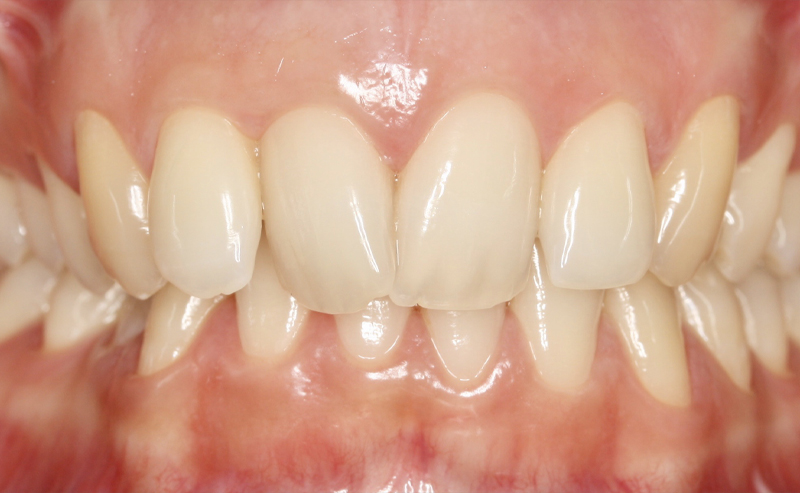

Fotografe a sua Boca de acordo com os exemplos abaixo demonstrados